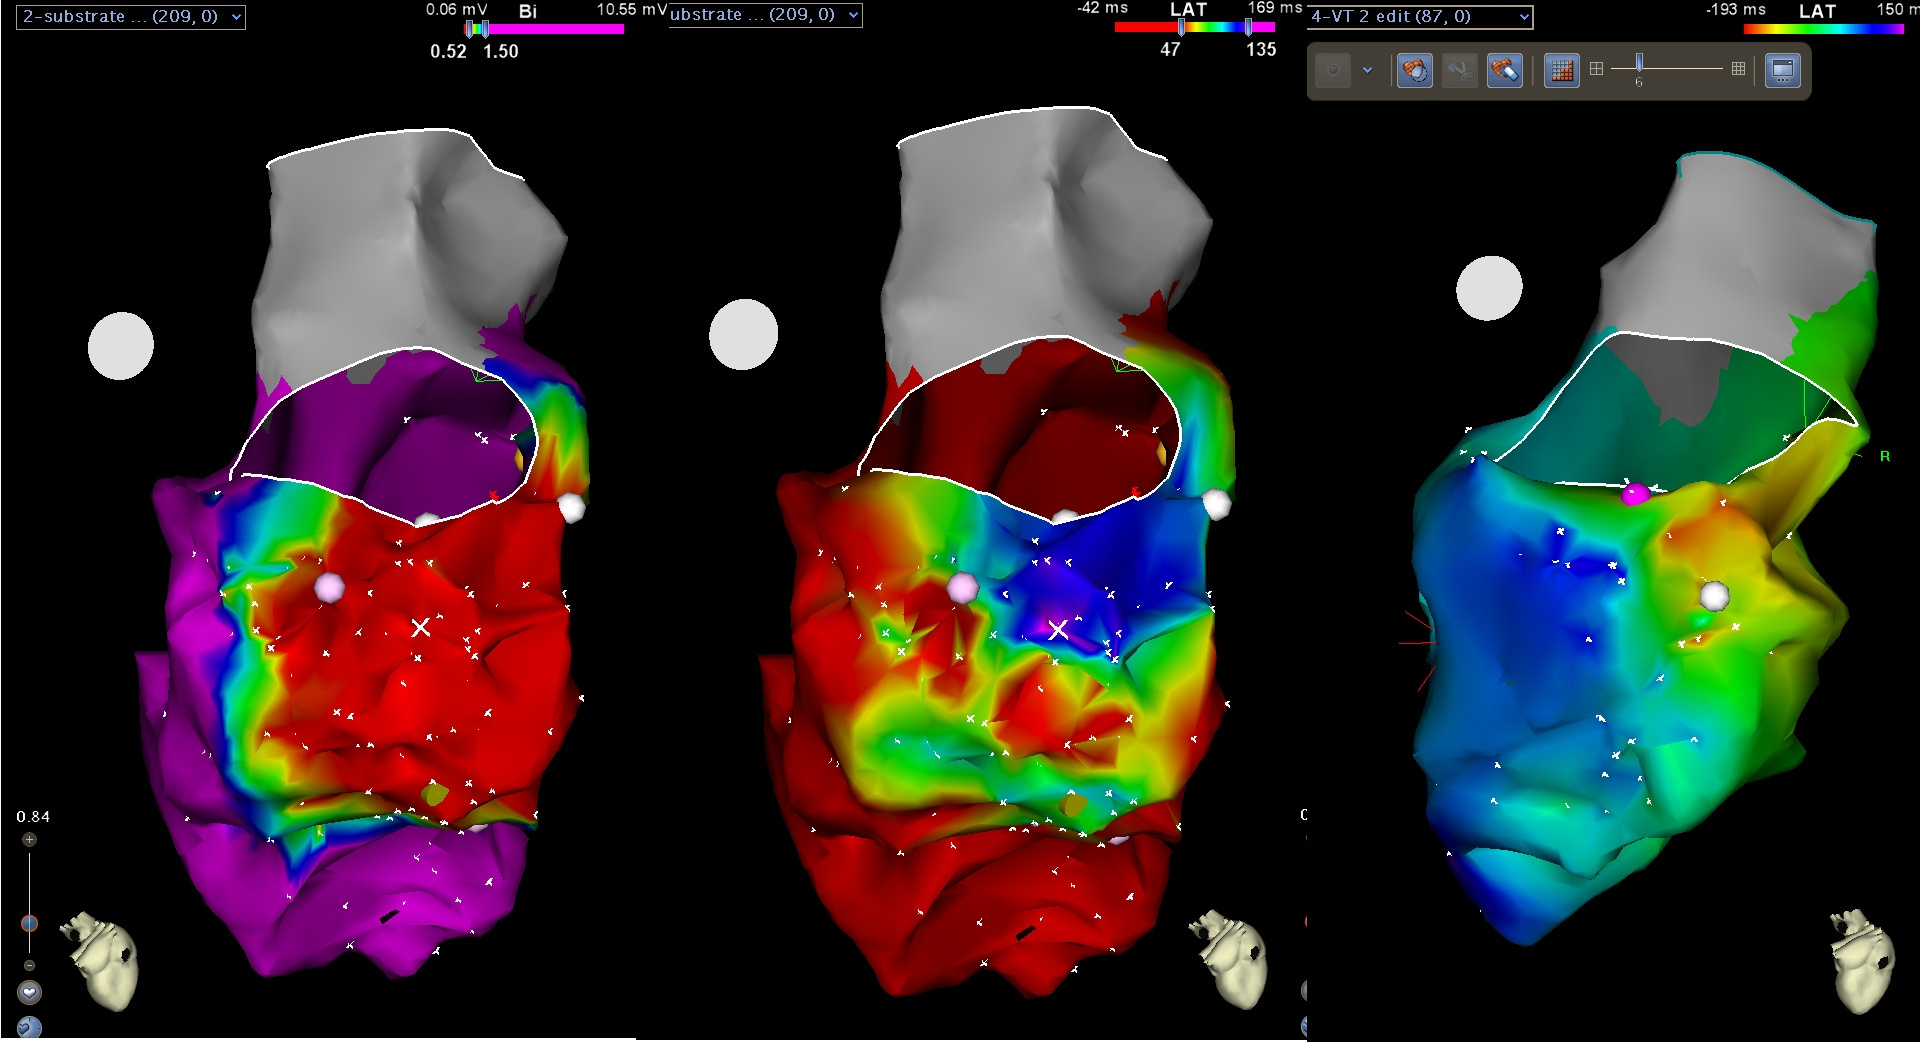

Combining information

scar_channel.jpg

Substrate - Late potentials

ldp_display.jpg